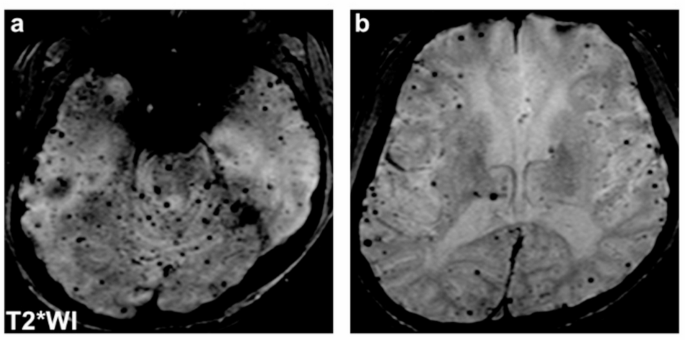

For imaging analysis, ABCC6-related CSVD was compared with CADASIL and referenced against the established CADASIL imaging phenotype. We did not designate the genetically undetermined group as a primary imaging comparator because the absence of known pathogenic variants does not exclude undetected or yet-to-be-identified genetic causes, rendering this group heterogeneous and therefore unsuitable as a primary imaging comparator. Brain MRI scans were acquired using 3.0 Tesla scanners across all centers. T2*-weighted images were primarily used for the evaluation of microbleeds; susceptibility-weighted imaging (SWI) was used when T2* images were not available (n = 1 in the ABCC6-related CSVD group, n = 2 in the CADASIL group). Minor variability in sequence parameters across centers may have existed, but all images were reviewed centrally to ensure consistency of evaluation. All scans were independently assessed by two authors (S.K. and S.A.), blinded to the patients’ genotypes and clinical information; disagreements were adjusted by a third author (M.U.), and final ratings were determined by consensus. Inter-rater reliability was not calculated because consensus ratings after adjudication were used. White matter hyperintensities were graded with the Fazekas scale; anterior temporal lesion severity was rated on a four-point scale (0–3) as described previously20. Lacunar infarcts and microbleeds were defined according to the Standards for Reporting Vascular Changes on Neuroimaging21.

The imaging features of ABCC6-related CSVD were distinct from those of CADASIL (Table 4). The ABCC6-related CSVD group had lower anterior temporal lesion scores (median [IQR]: 0 [0–0] vs. 2 [0–3], P = 0.004). The number of lacunar infarcts tended to be lower in the ABCC6 group but did not differ significantly between the groups (median [IQR]: 1 [0–8] vs 7.5 [2.8–13.3], P = 0.106). By contrast, a significantly higher cerebral hemorrhage rate was observed in the ABCC6-related CSVD group than in the CADASIL group (55.6% vs. 11.9%, P = 0.010), particularly in the infratentorial (22.2% vs. 0%, P = 0.028) and lobar (33.3% vs. 2.4%, P = 0.014) regions. The proportion of patients with multiple microbleeds was also higher in the ABCC6-related CSVD group (77.8% vs. 28.6%, P = 0.010). In the ABCC6-related CSVD group, microbleeds were frequently observed in the lobar region (median [IQR]: 8.5 [0.8–20] vs. 0.5 [0–4.8], P = 0.031), similarly to intracerebral hemorrhages. A trend toward increased microbleeds in the infratentorial regions was observed in the ABCC6-related CSVD group, although the difference was not statistically significant (median [IQR]: 2 [0.75–8.5] vs. 0 [0–1.8], P = 0.050) (Figs. 1 and 2).

Imaging characteristics of hemorrhagic lesions in ABCC6-related cerebral small vessel diseases (CSVD) and cerebral autosomal dominant arteriopathy with subcortical infarcts and leukoencephalopathy (CADASIL). Violin plots showing the number of microbleeds (MBs) between two groups: (a) total, (b) lobar, (c) infratentorial, and (d) deep MBs. (e) A bar chart showing multiple MBs prevalence between two groups. Statistical analyses used the Wilcoxon rank-sum test (a–d) and Fisher’s exact test (e). P < 0.05 was considered significant.